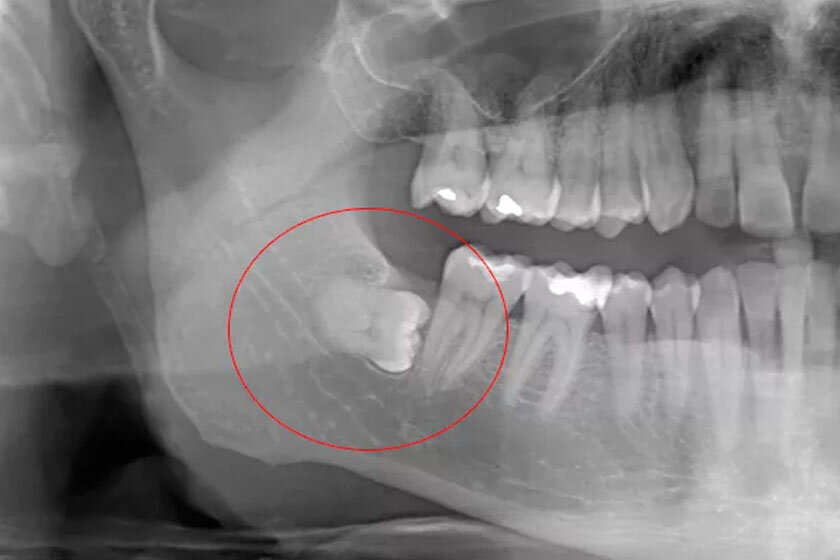

• неправильное расположение зуба в челюсти (под наклоном или горизонтально);

Нередко прорезыванию третьих моляров мешают соседние зубы. «Семёрки» могут быть наклонены в сторону роста зубов мудрости, или же сама коронка «восьмёрок» может упираться в корень второго моляра. Установить точную причину отсутствия зубов можно с помощью лучевой диагностики.

Если единица расположена правильно и не имеет серьезных патологий, удалить ее будет несложно. Чтобы провести удаление без риска осложнений, перед процедурой пациенту назначают сделать снимок зуба.

• Однако чаще всего третий моляр растет неправильно, прорезывается частично или переплетается с соседними корнями. В этом случае вмешательство будет проводиться сложным способом. Окончательное решение о выборе метода врач принимает после осмотра и получения результатов рентгена зуба.